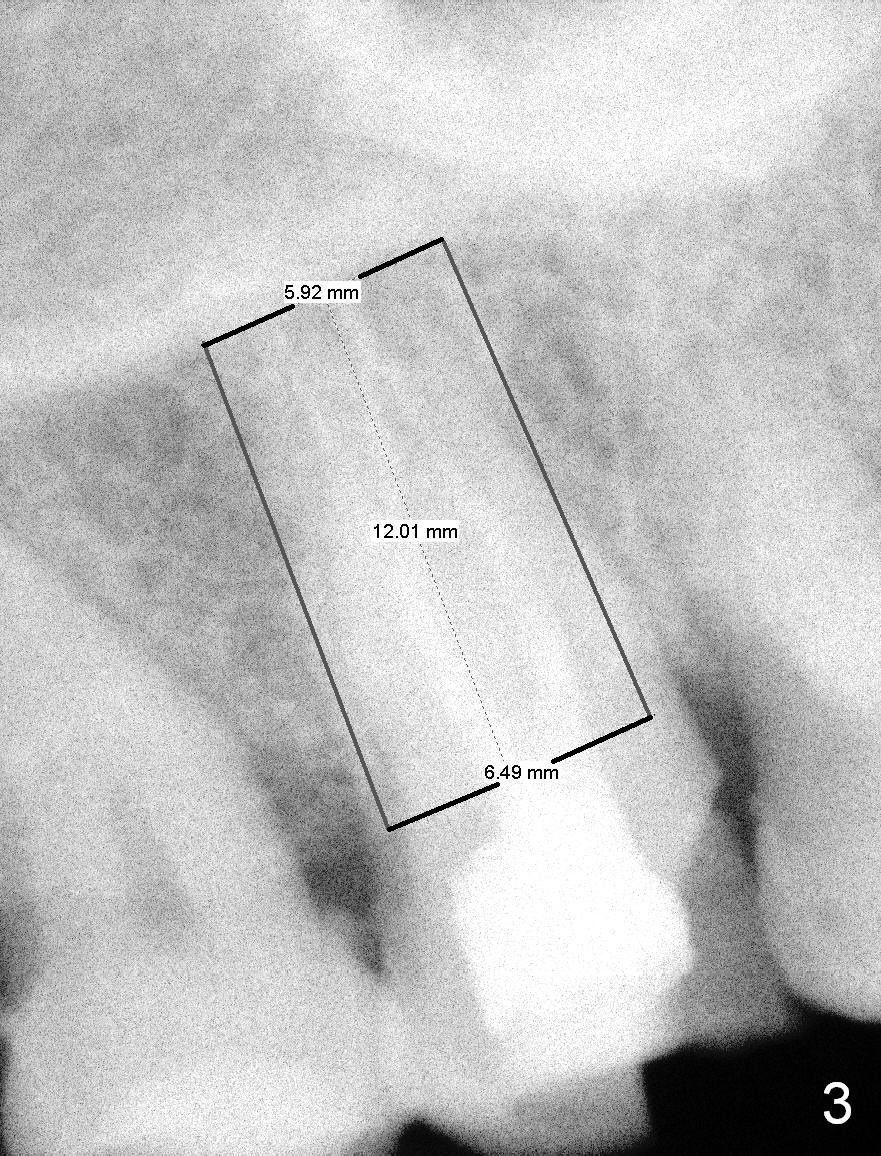

A 65-year-old lady is at early stage of Parkinson's disease and appears to be a bruxer. There are multiple chipped teeth, including #2 (Fig.1,4 *). She chooses implant over RCT retreat. A tissue-level implant (Fig.2) matches the root shape of the affected tooth better than a bone-level one (Fig.3), because of taper. The buccopalatal and mesiodistal dimensions of the extraction socket are 11 and 8 mm, respectively (Fig.5,7).

The buccal roots are fused. The buccal socket (BS) seems to be larger than the palatal one (PS). There is a septum (S) between the 2 sockets. Both the buccal and palatal plates (BP, PP) are intact. The anatomy is illustrated in Fig.6a (buccopalatal section) with the same abbreviations, mentioned above. SF: sinus floor.

Osteotomy for immediate implant is initiated with a 2 mm pilot drill (Fig.6b red arrow) in the coronal end of the buccal slope of the septum (center of the socket). Once the drill gets initial penetration, the trajectory changes to the long axis of the tooth (Fig.6c). Then PA is taken with a parallel pin (Fig.7). It appears that the depth is not enough; there is bone apical to the pin. As osteotomy increases in diameter, burs may be deviated buccally due to the septal buccal slope (to be discussed below). With longer osteotomy, the deviation may be less. Osteotomy is deepened (Fig.6d). From this moment on, nose blowing test is done after each step. The result is all negative. As drill diameter increases, they do deviate buccally (Fig.6e arrow), since there is less bone contact buccally than lingually (compare Fig.6e,f). With the same reason, smaller tapered taps (Fig.6g pink, 5 and 6 mm) tend to be mobile buccally (arrow). When a large tap (7 mm) is inserted (Fig.8), there is no buccal mobility. It appears that the tap contacts more of the buccal plate (Fig.6h), but the coronal end of the tap is buccal (Fig.6i, pink circle). At each step of osteotomy, the coronal end of a bur or tap should be pushed as lingual as possible so that the final tap is favorable for restoration (Fig.6j). Sinus lift is done (Fig.6k red circle; Fig.9 *) before placement of 7x17 mm implant (I, >60 Ncm). Since the palatal socket is not associated with implant stability, it is closed by collagen plug (Fig.6l, blue area). As extra precaution, bone graft is placed around the coronal portion of the tissue-level implant (Fig.6l red circles), followed by collagen dressing.